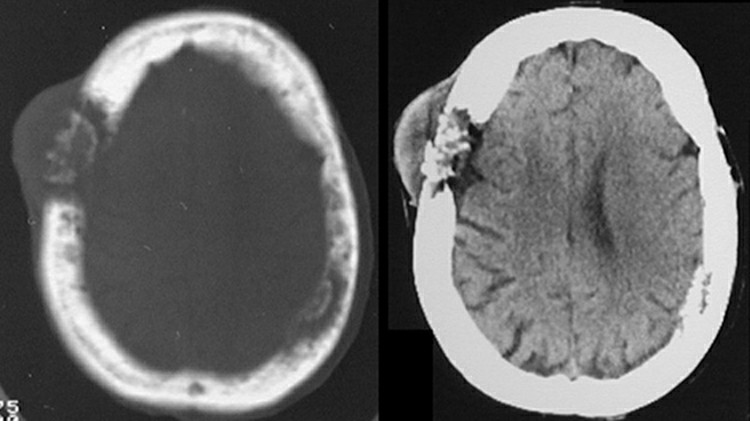

Testes e Diagnóstico de Metástase Óssea: Os testes de imagem são usados para investigar sinais e sintomas que podem indicar Metástase Óssea. Quais testes você sofre depende da sua situação específica. Os testes podem incluir:

- Raio X

- Escaneamento ósseo (cintilografia óssea)

- Tomografia computadorizada (CT)

- Ressonância magnética (MRI)

- Tomografia por emissão de positrões (PET)